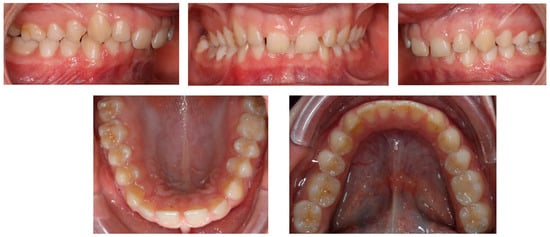

A short periodontal examination, performed in our clinic in this kind of patient was performed. No need for further specialist examination was reported. The periodontal biotype and oral hygiene were both established as correct (Figure 2).

Figure 2. Pre-treatment intraoral photos (the upper line—right, mid, and left occlusion, the lower line—upper arch and lower arch forms).